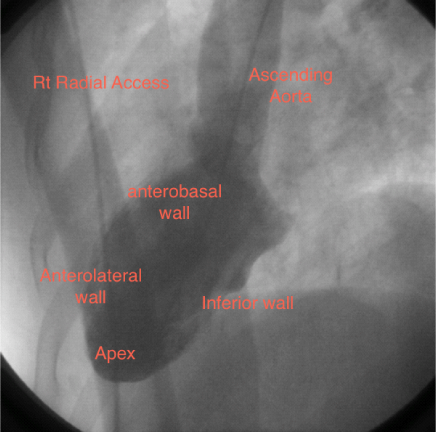

A 55-year old man was transferred from one of our referring hospitals with early post infarct unstable angina, having chest pain in the right side of the chest radiating to the right shoulder and the back, following an anterior ST-elevation myocardial infarction for which he had received thrombolytic therapy. He was a known case of dextrocardia with Kartagener syndrome, diabetic and smoker. Physical examination was unremarkable except for findings consistent with dextrocardia. Apart from raised troponine-I and blood sugar, his routine laboratory tests were within normal values. 12-lead Electrocardiogram (ECG) showed a negative P wave lead-I and aVL and positive P and R waves in aVR together with Q waves in inferior leads. Reversed chest leads showed QS in V1-V3 with ST depression in V4-V6 associated with deep T wave inversion. Chest X-ray revealed dextrocardia with a right-sided aortic knob as well as gastric bubble. Echocardiography revealed left ventricle ejection fraction of 40% with hypokineses correspondent with ischemia in left anterior descending artery (LAD) territories and no significant valve disease. Cardiac catheterization was performed via the right radial artery using mirror-image views and standard Judkins catheters. A 5 French (Fr) angulated pigtail catheter was through the right-sided aortic knob into the left ventricle. The 300 left anterior oblique (LAO) ventriculogram (Figure 1) showed anterior wall hypokinesia and severe hypokises/akineses of the apex and the inferior wall with an ejection fraction of 40%. The ostium of the right coronary artery (RCA) was easily engaged by gentle counterclockwise rotation and slightly withdrawal of a 5 Fr Judkins right 4 cm (JR4) diagnostic catheter in right-anterior-oblique (RAO) and RAO-cranial views showed 100% lesion at mid-RCA segment (Figure 2). The ostium of the left main coronary artery was also cannulated using a 5 Fr Judkins left 4-cm (JL4) diagnostic catheter in a RAO view. The selective left coronary angiogram revealed a>70% tubular stenosis in the middle segment of LAD artery and a patent left circumflex (LCX) artery (Figure 3). Adhoc-PCI to LAD was performed with the use of 5 Fr JL 3.5 guide catheter and a 0.014” balanced middleweight (BMW) guide wire. Two overlapping drug-eluting stents (Xience Prime 2.5x28mm and Promus Element 2.25x12mm) were directly deployed at the site of the lesion in the middle segment of the LAD artery with good angiographic result (Figure 4). The patient experienced an uneventful post-PCI course and was discharged on the following day. He was free of angina on clinical follow-up.

Figure 1 Left ventricle angiogram in left anterior oblique view 30˚ showing mirror image anatomical configuration of the left ventricle in conventional right anterior oblique 30˚ view.